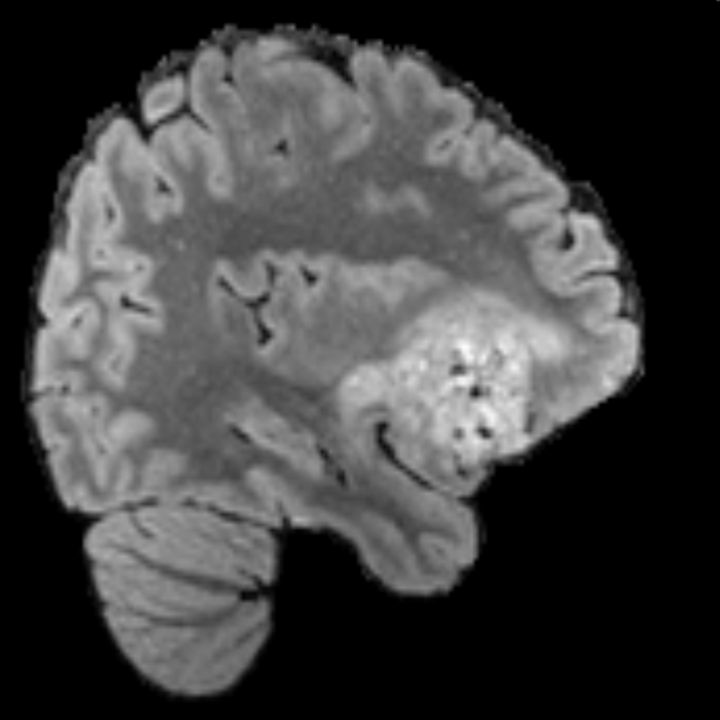

Preservation of Spine Curvature. For the spine segmentation on UK Biobank, we use a UNet++ model [81] with Dice Loss and use the curvature prediction of the spine followed in [9]). We measure the Pearson correlation factor [9] of spine curvature measured on the generated MRIs where the input is a single MRI coronal slice, or a single sagittal slice against the curvature of reference real MRIs of the same samples. The correlation coefficients are 0.89 for the coronal MRIs and 0.88 for the sagittal MRIs on the test set of 308 human-annotated angles.

B.3 Preservation of Spine Curvature and Fat

For the spine segmentation on UK Biobank, we use a UNet++ model [81] with Dice Loss. We use a model trained to predict curves on DXA on UK Biobank [9]. We show in Figure 20 that generated MRIs preserve the spine curvature from normal to severe scoliosis cases. We also study the case when DXA is used to generate the MRIs and show in Figure 14 how the correlation to real curvatures compares to the input MRI case. The curvatures of the MRI generated from the coronal plane match the DXA curvatures more than the curvatures generated from sagittal MRI. This is expected since the antero-posterior plane of DXA is equivalent to the coronal plane for MRIs. This also explains the greater Pearson’s correlation coefficient of the coronal MRI (0.89) and DXA-generated curvature (0.88) compared to sagittal-generated curvature (0.87) relative to the reference curvature on the coronal plane. We observe though that MRI generation using X-Diffusion from another plane than the conventional plane for scoliosis assessment is valid.

For the spine segmentation on UK Biobank, we use a UNet++ model [81] with Dice Loss. We use a model trained to predict curves on DXA on UK Biobank [9]). We measure the Pearson correlation factor [9] of spine curvature measured on the generated MRIs where the input is a single MRI coronal slice, a single sagittal slice, or from the paired DXA, against the curvature of reference real MRIs of the same samples. The correlation coefficients are 0.89 for the coronal MRIs, 0.88 for the sagittal MRIs, and 0.87 for the DXAs on the test set of 308 human-annotated angles. We can then bin the curvature, , of the spines under different scoliosis categories based on human-annotated angles: mild: , moderate: , and severe . We show the results in Figure 20. This illustrates that the generated MRIs preserve the spine curvature from normal to severe scoliosis cases.